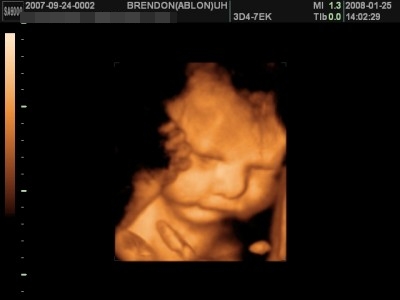

Amúgy a lányomról a 34. héten a Brendonban jó képek készültek, 44-et írt ki a pasi és kaptam dvd-t is, mind ilyen, úgyhogy megnyugtatásul - ráfér a feje, legalábbis az arcocskája ha nagyobb lesz, akkor is:

Kép